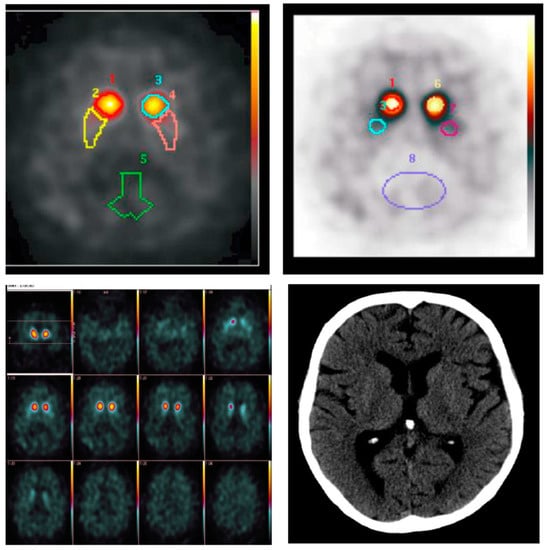

2. Case Report